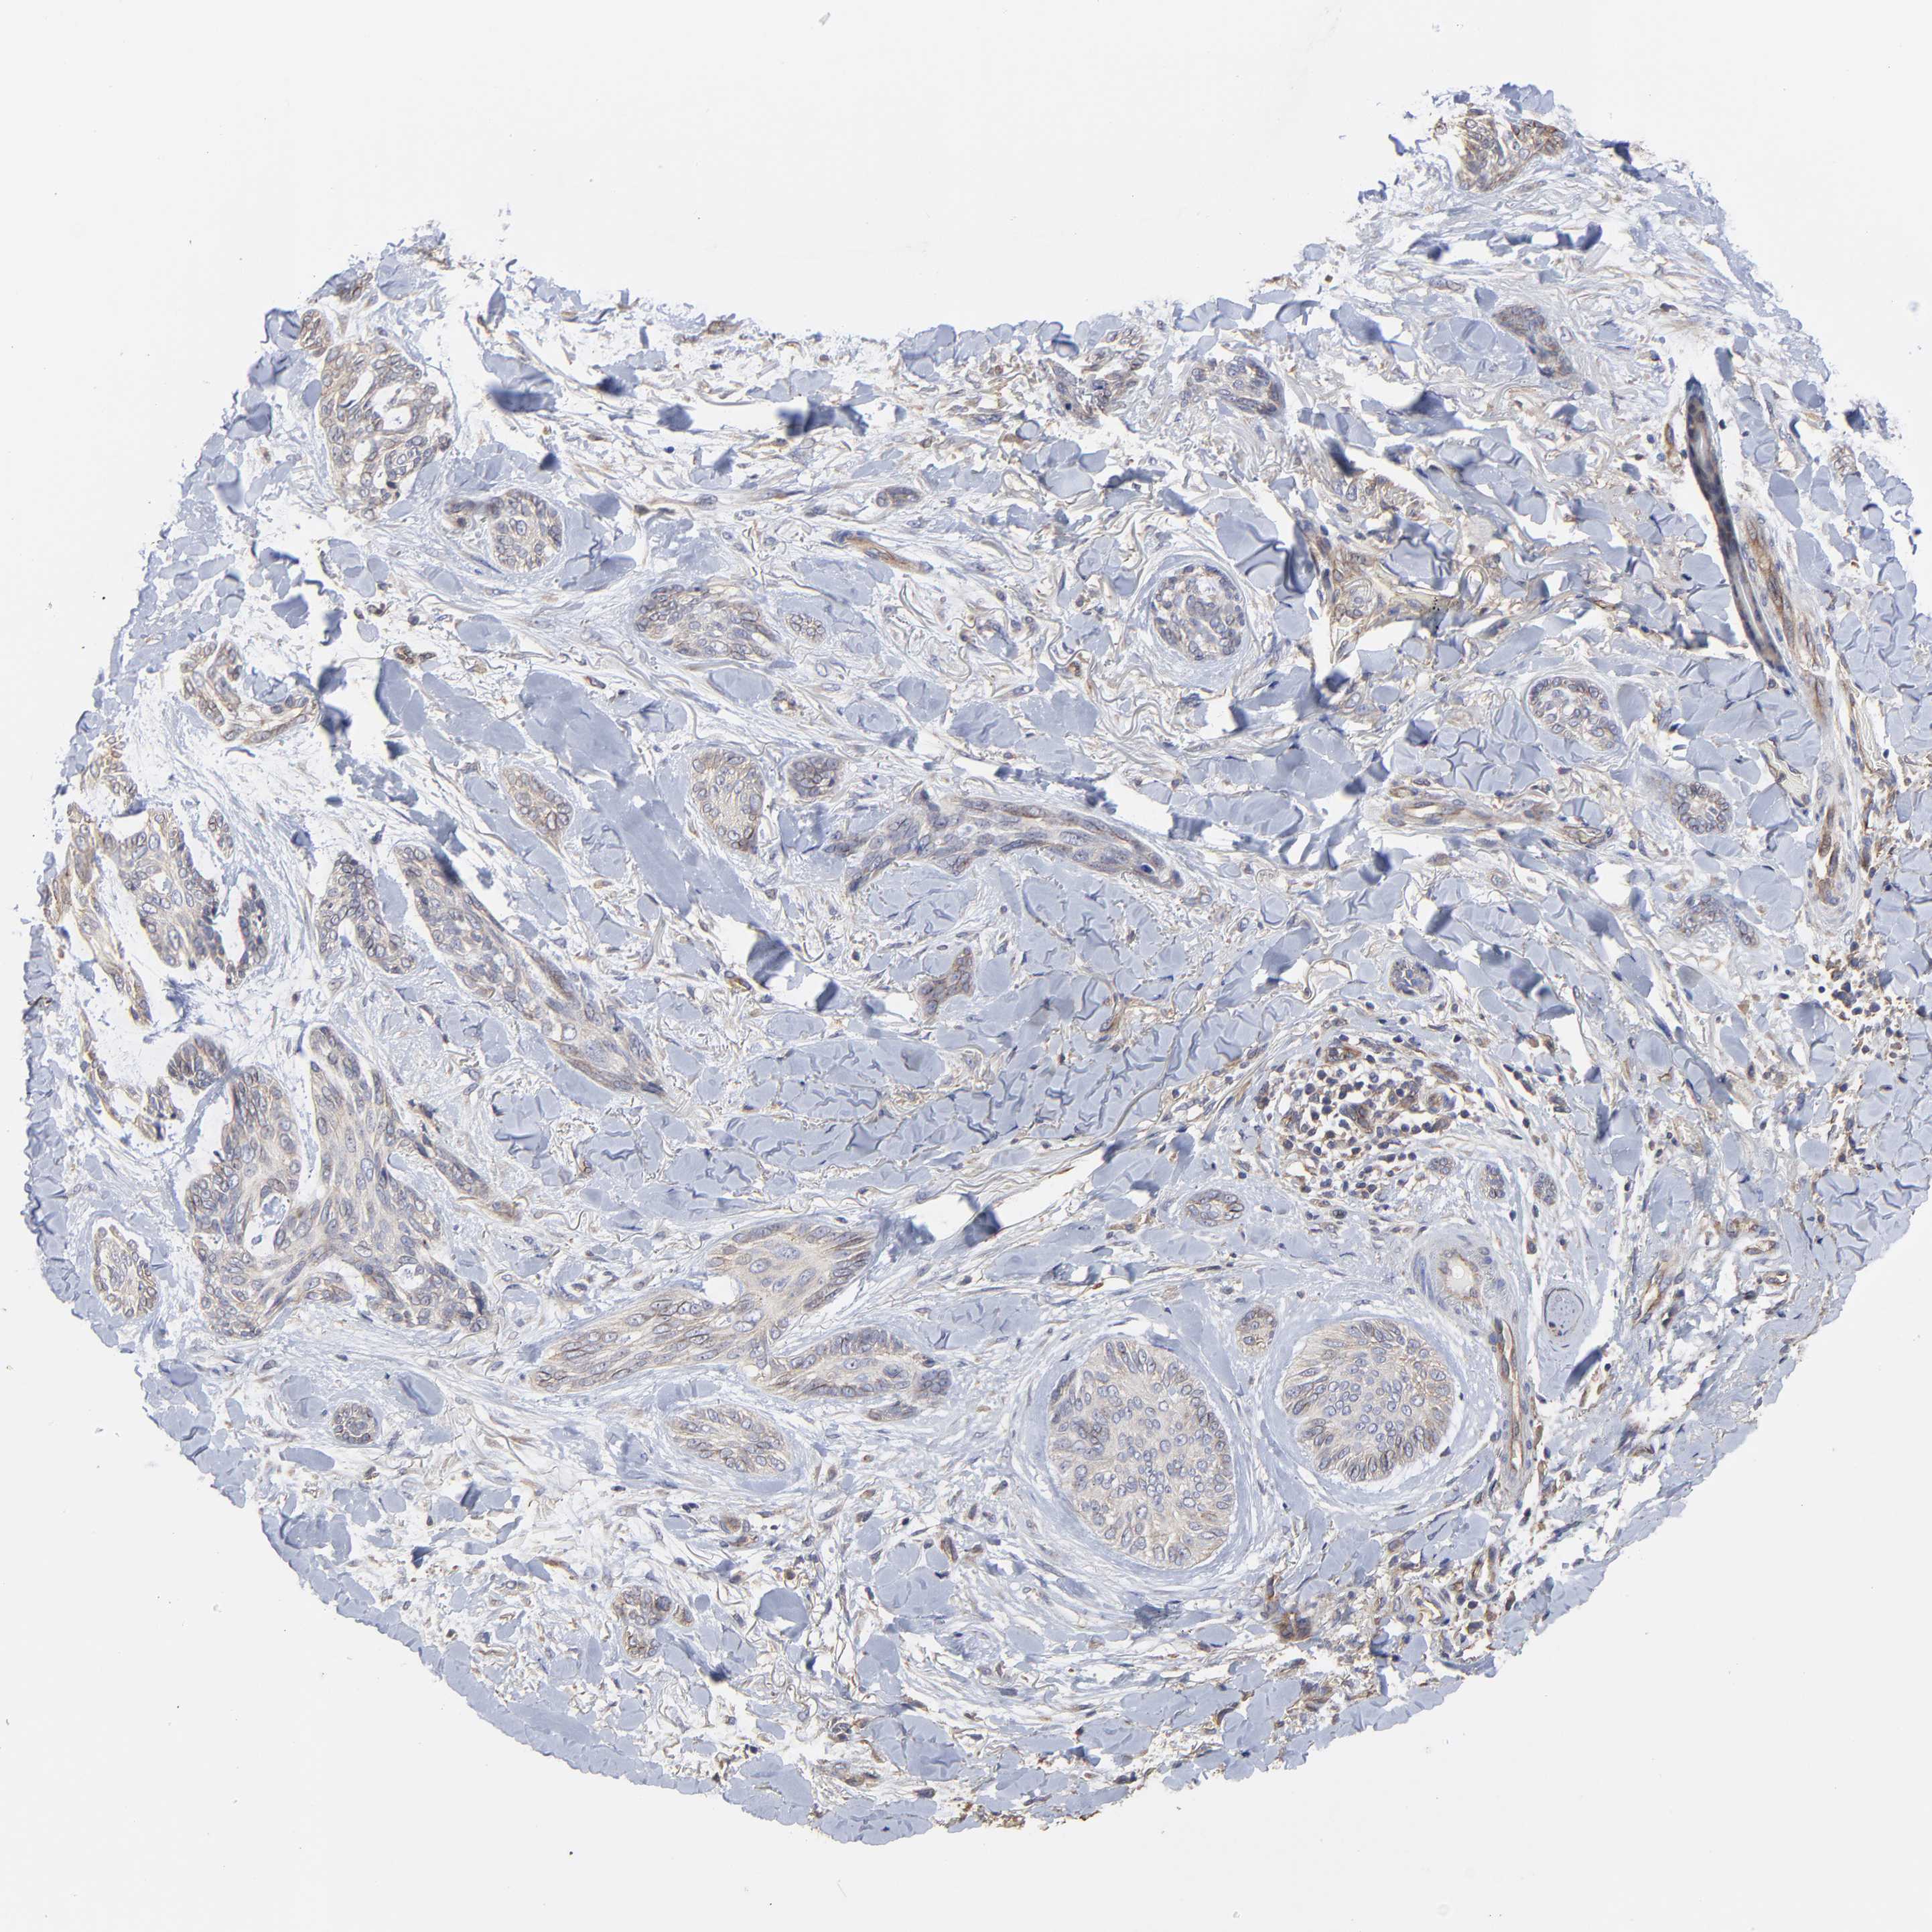

SKIN CANCER - Protein expressioni

A mouse-over function shows sample information and annotation data. Click on an image to view it in a full screen mode. Samples can be filtered based on level of antibody staining by selecting one or several of the following categories: high, medium, low and not detected. The assay and annotation is described here.

Antibody stainingi

Antibody staining in the annotated cell types in the current human tissue is reported as not detected, low, medium, or high, based on conventional immunohistochemistry profiling in selected tissues. This score is based on the combination of the staining intensity and fraction of stained cells.

Each image is clickable and will lead to virtual microscopy that enables deeper exploration of all samples and also displays staining intensity scores, fraction scores and subcellular localization as well as patient and tissue information for each sample.

Antibody HPA003004

Squamous cell carcinoma, NOS

Basal cell carcinoma

Squamous cell carcinoma in situ, NOS

Squamous cell carcinoma, metastatic, NOS